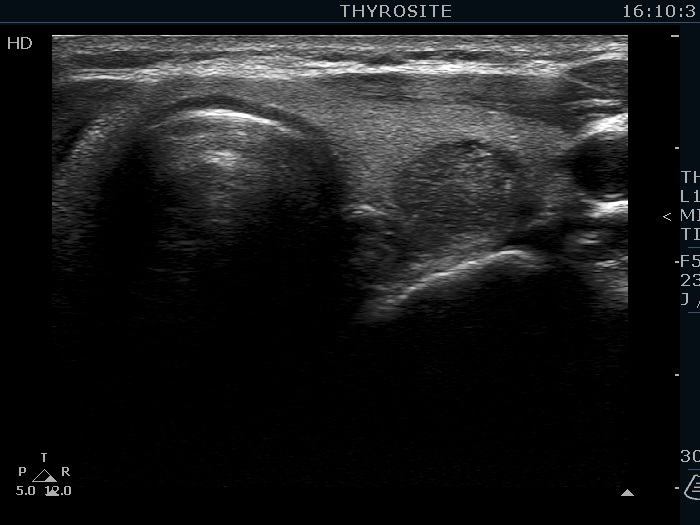

Ultrasonography. The thyroid was echonormal. There were several hypoechoic nodules in the left lobe. The middle one had back wall cystic figures. There were 3 or four discrete, deeply hypoechoic lesions above and lateral to the left lobe in the neck. One of them presented with a hilum-like figure while the others lacked hilum.